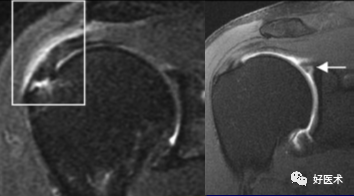

冈上肌肌腱撕裂可分为全层或部分,部分撕裂又分为下表面(关节面)撕裂、上表面(滑囊侧)撕裂及腱内撕裂。据文献报道,冈上肌肌腱下表面撕裂最常见,可为上表面撕裂的2~3倍,腱内撕裂则最少见。

冈上肌肌腱下表面撕裂发病率高可能与肩关节不稳并内撞击,肩关节侧肌腱纤维延展性较差有关。

诊断冈上肌肌腱部分撕裂的金标准是肩关节镜,但是腱内撕裂常易漏诊。

冈上肌腱不完全撕裂

冈上肌腱不完全撕裂伴肩峰下囊积液